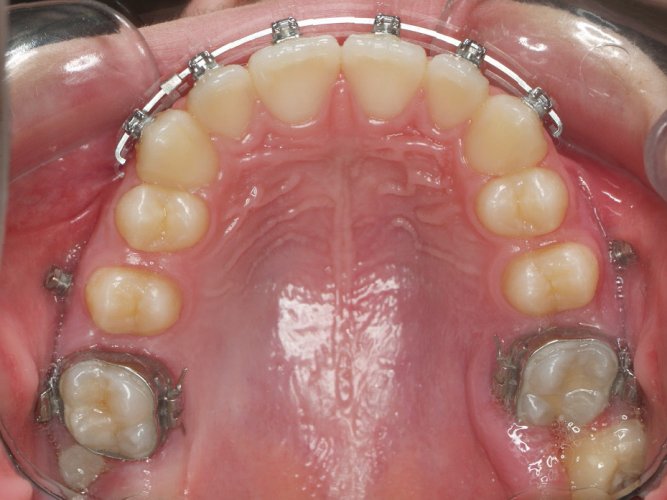

Paciente de 14 años, acude a nuestra consulta por dientes superiores proclinados hacia delante y apiñamiento. El paciente presenta una full clase 2, sobremordida y dientes inferiores proclinados. Decidimos colocarle brackets Damon y microtornillos en maxilar superior para distalizar las muelas. La duración del tratamiento fue de  24meses, y ahora lleva 1 año de contención. El paciente se pone la férula Essix superior 1noche/2 y la de abajo 1noche/semana para mantener.

MARZO 2013-Upper Occlusal

Image 4 De 4